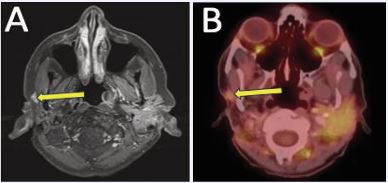

A 43-year-old woman with a history of cT2 ACC of the right lower lip was initially treated with EBRT (50 Gy) followed by an HDR-ISBT boost (20 Gy). She subsequently developed metastatic disease, managed with multiple lines of systemic therapy. Despite ongoing systemic therapy, approximately three years after completion of definitive radiotherapy, she presented with progressive enlargement and pain at the primary site. Contrast-enhanced face CT demonstrated nodular soft tissue thickening of the right lower lip measuring 0.8 cm (Figure 8A, B).

https://www.jscimedcentral.com/public/assets/images/uploads/image-1766379757-1.JPG

Figure 8 Recurrent right lower lip ACC demonstrated on contrast-enhanced face CT in (A) axial; and (B) coronal views. Repeat imaging one year later with interval growth, in (C) axial; and (D) coronal views. Contrast-enhanced face MRI four months later showing continued progression in (E) axial; and (F) coronal views.

Over the next year, imaging showed continued progression and necrosis with enlargement to 1.6 cm (Figure 8C, D). The lesion was closely adjacent to the right mental foramen without evidence of retrograde perineural spread along the inferior alveolar canal. Four months later, contrast enhanced face MRI demonstrated further enlargement up to 2.3 cm (Figure 8E, F).